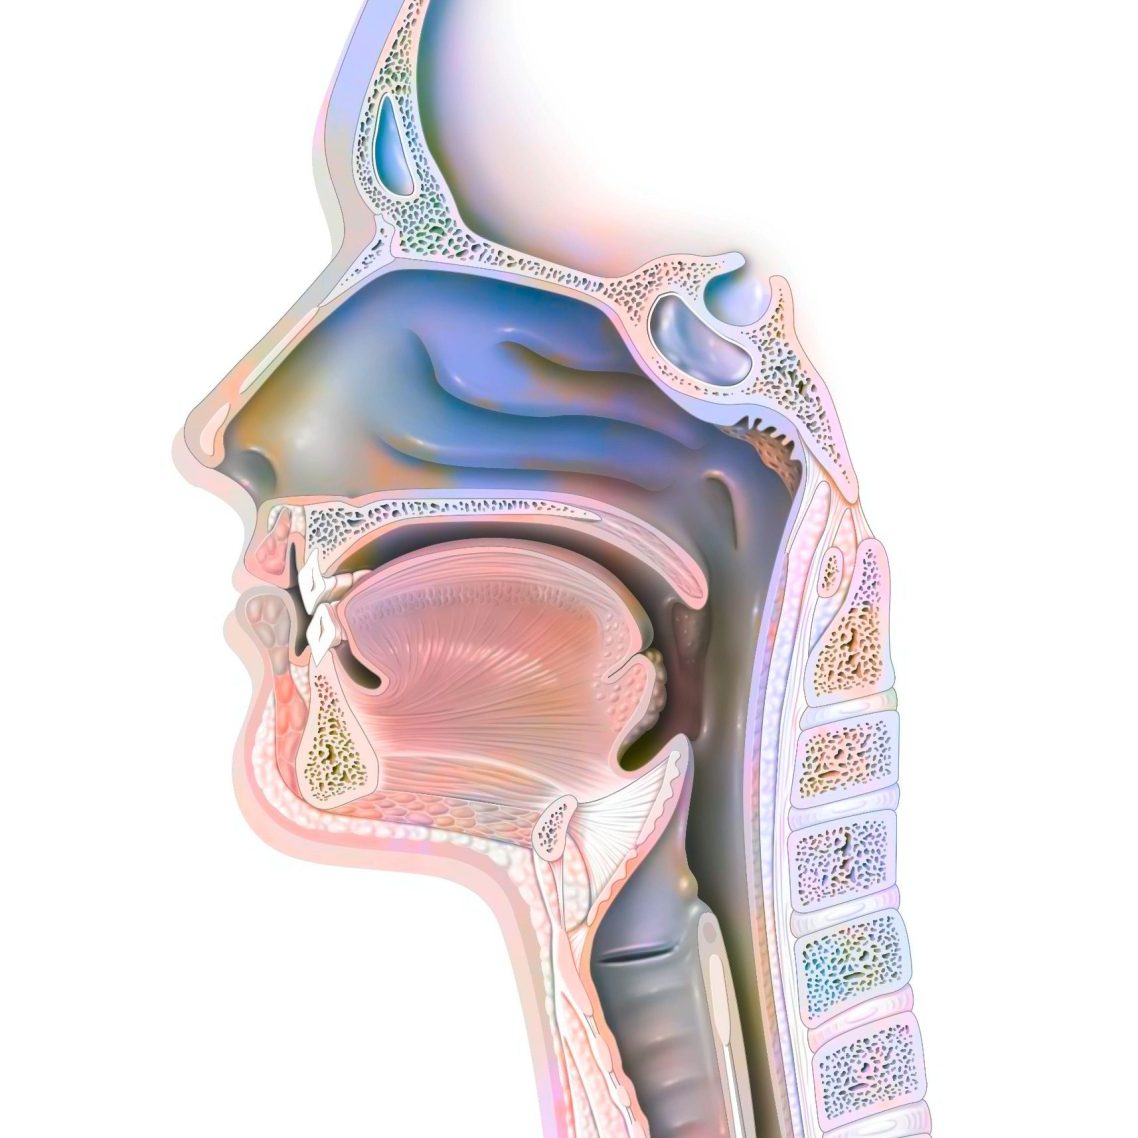

- Sprach-, Sprech- Stimm- und Schlucktherapien für (ausschließlich) Privatpatienten und Selbstzahler

- Schulungen und Beratungen im Fachgebiet der Sprach-therapie/Logopädie (Schwerpunkte: Dysphagien, TK-Management und Dysphonien)

Sprache, Stimme und Schlucken sind essenzielle Elemente menschlicher Kommunikation und Lebensqualität. In meiner Arbeit als klinische Linguistin ist es mein Ziel, Menschen zu unterstützen ihre Fähigkeiten in diesen Bereichen zu entwickeln, wiederzuerlangen oder zu bewahren. Mit einem ganzheitlichen Ansatz, der wissenschaftliche Expertise und Empathie vereint, setze ich mich dafür ein, jedem meiner Patienten eine individuelle und gezielte Therapie zu bieten.